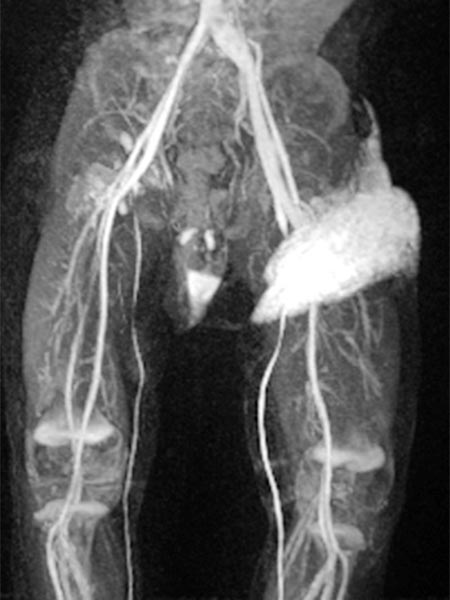

Kontrastmittelunterstützte, dynamische MR-Angiographie (koronare Schichtführung).

30 s nach KM-Injektion in der früharteriellen Phase kommt es zu einem sofortigen, frühen Enhancement des Tumors in der linken Leiste.

41 s nach KM-Injektion in der spätarteriellen Phase kommt es zu einem weiteren, eher diffusen, starken Enhancement des Tumors („tumor-blush“) in der linken Leiste, entsprechend einem soliden Gefäßtumor.

57 s nach KM-Injektion in der frühen venösen Phase reichert der gesamte Tumor weiterhin stark an. Es kontrastiert sich jetzt auch eine im Seitenvergleich stark erweiterte frühe Drainagevene. Durch die starke Tumorperfusion mit erhöhtem venösen Abstrom hat sich die venöse Drainage (Venae iliacae links) dilatiert.

130 s nach KM-Injektion in der späten Phase bleibt das starke Enhancement des Tumors in der linken Leiste erhalten, kein frühes „wash-out“. Auch die erweiterte venöse Drainage über die linken Iliakalvenen kontrastiert nach wie vor.